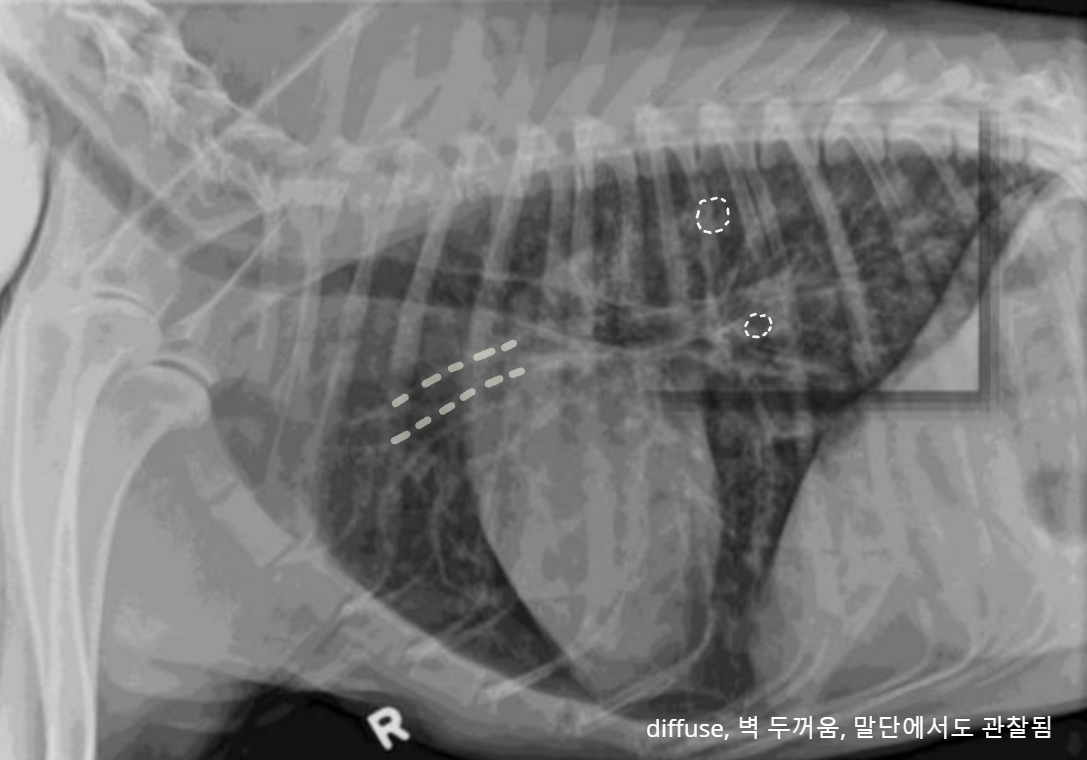

| โณ๏ธ Bronchial pattern (๊ธฐ๊ด์ง ํจํด) | |

| ์ผ์ฆ ์ธํฌ ์นจ์ค์ผ๋ก ๊ธฐ๊ด์ง๋ฒฝ ๋๊บผ์์ง - Doughnut sign : end-on - Tramline sing : side-on ์์ธ - Bronchitis (๋ง์ฑ) - Allergic (Feline asthma, ์๋ฌ์ง์ฑ ํ๋ ด) - Immune-mediated (PIE) ์ฃผ์ - ๋ณด์ธ๋ค๊ณ ํด์ ๋ฌด์กฐ๊ฑด ์ง๋ณ์ X - ๋ง๋จ์์ ๋ค์ ๊ด์ฐฐ๋๋ฉด ์ง๋ณ ๊ฐ๋ฅ์ฑ โ | ![]() ![]() |

| ๊ด๋ จ ์ง๋ณ 1) CCB (Canine Chronic Bronchitis) - ๋ง์ฑ์ ์ธ dry cough - ๋ด๊ฐ์ด ์ข์์ ธ ํธํก ๊ณค๋ | |

| ๊ด๋ จ ์ง๋ณ 2) Bronchiectasis - ๊ธฐ๊ด์ง๊ฐ ํ์ฅ๋๋ค๊ฐ ํ๋ ฅ์ ์๊ณ ํ๋ฌผํด์ง - ๋ง์ฑ์ ์ด๋ฉฐ, ์๊ตฌ์ . ์น๋ฃ ๋ถ๊ฐ. - ํ๋ ด ๋ฐ์ํ๊ธฐ ์ฌ์, ์น๋ช ์ . | ![]() |